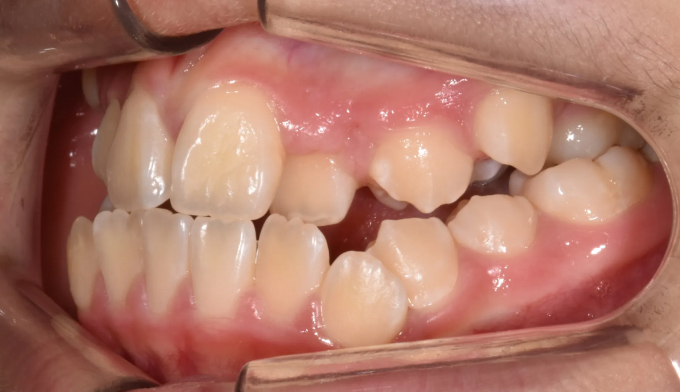

송곳니가 원래 나와야 할 공간이 없다보니 작은 어금니 위치로 이동해서 맹출하고 있습니다. 이를 치아 전위라고 합니다.

이와 더불어 좁은 위턱 악궁은 얼굴 전체의 비대칭을 유발하고 있고, 아래턱의 과성장은 주걱턱 경향까지 보이고 있습니다.

이미 송곳니와 작은어금니의 위치가 꽤 많이 바뀐 상태에서 치과에 내원하게 되어 어쩔 수 없이 최종적인 위치를 바꿔서 배열합니다. 씹거나 말하는데는 전혀 문제가 없습니다.